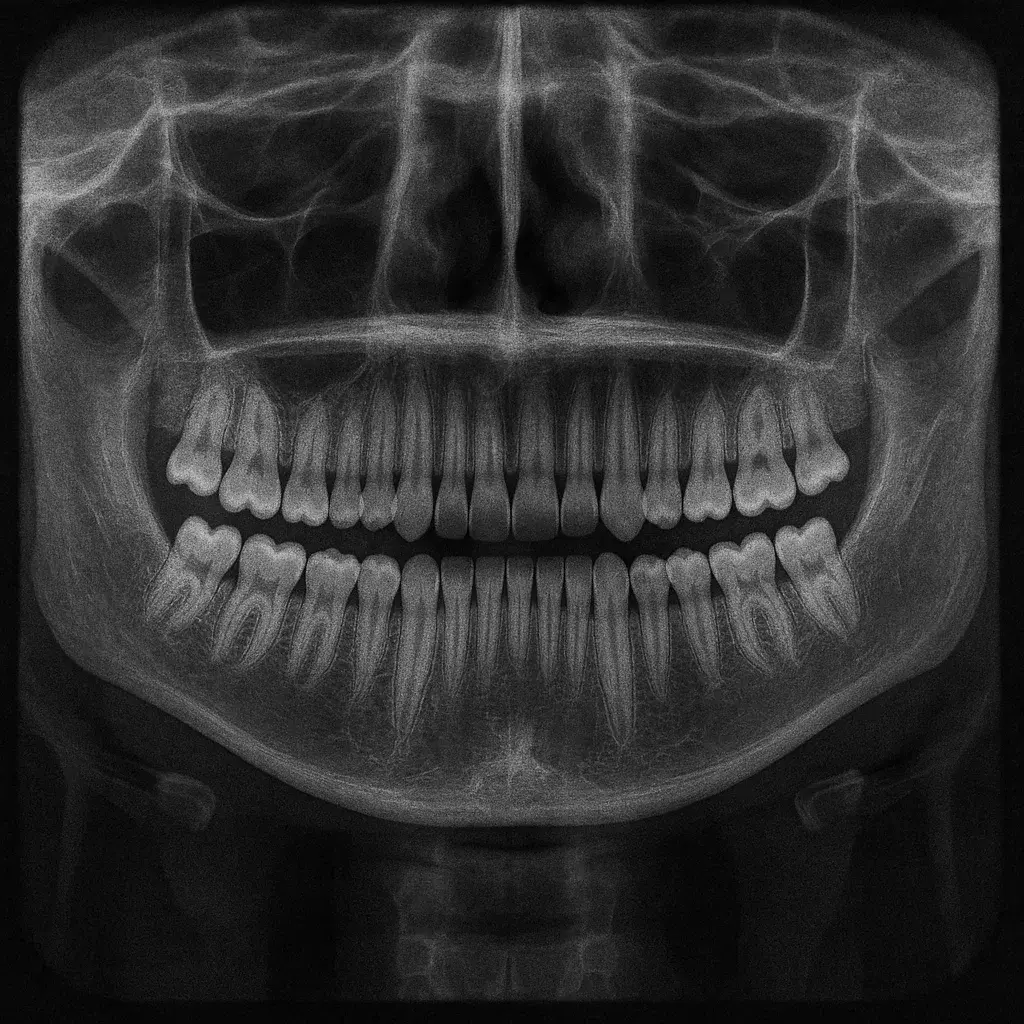

На первом приёме проводится компьютерная томография (КТ) и панорамный снимок — это помогает точно оценить состояние зубов, десен и челюстей. После этого врач снимает восковой слепок, подбирает подходящую брекет-систему и составляет индивидуальный план лечения с графиком коррекций. Такой подход обеспечивает максимальную точность и предсказуемый результат.